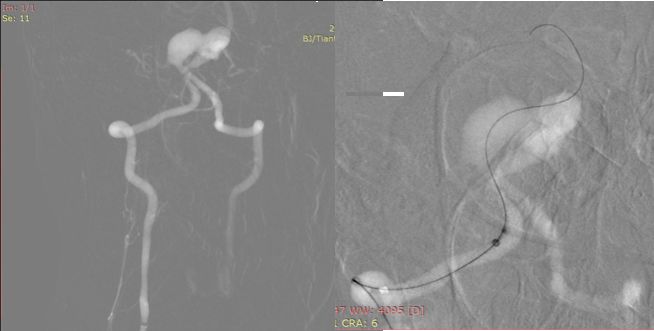

术前右椎动脉造影显示:基底动脉中下段巨大夹层动脉瘤存在,PED支架向下移位脱落至基底动脉下段。

术前右椎造影:

术前右椎动脉路途下显示PED 支架向下回缩,支架近心端回缩不明显。远心端至动脉瘤下。箭头所示为支架远端脱落至动脉瘤内的位置。